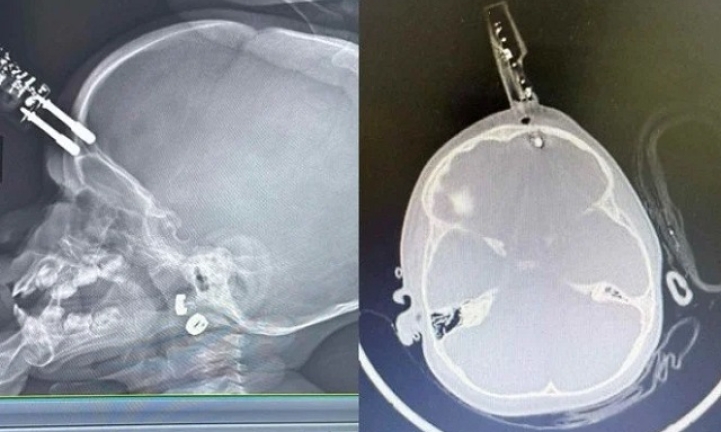

DIVINÓPOLIS, MG - Uma criança de 1 ano e 4 meses teve um carregador de celular cravado na cabeça após cair da cama dentro de casa, em Divinópolis, no Centro-Oeste de Minas Gerais. O objeto perfurou a região frontal do crânio, próximo aos olhos, e atingiu o cérebro, o que levou a uma cirurgia de emergência. Após cinco dias de internação, a criança recebeu alta hospitalar.

A criança foi levada inicialmente para a UPA de Divinópolis e, diante da gravidade, transferida pelo Samu para a sala vermelha do Hospital São João de Deus. Exames de imagem confirmaram que o pino havia transfixado o osso do crânio e atingido o cérebro. “O osso do crânio nessa idade é muito fino, tem apenas alguns milímetros. Pela tomografia, vimos que o objeto atravessou a calota craniana e lesionou a ponta do lobo frontal”, detalhou Bruno Castro.

Apesar da gravidade do ferimento, a criança estava consciente e foi levada imediatamente ao centro cirúrgico. O procedimento ocorreu sem intercorrências. “Foi uma cirurgia rápida e tranquila. Retiramos o corpo estranho, estancamos um pequeno sangramento e fizemos a correção da lesão. Ela acordou bem da anestesia e foi encaminhada ao CTI pediátrico”, afirmou o neurocirurgião.

A criança permaneceu 36 horas em observação intensiva e, após nova tomografia sem sinais de sangramento intracraniano, seguiu para a enfermaria. Por protocolo, recebeu antibiótico venoso durante cinco dias para prevenir infecções.